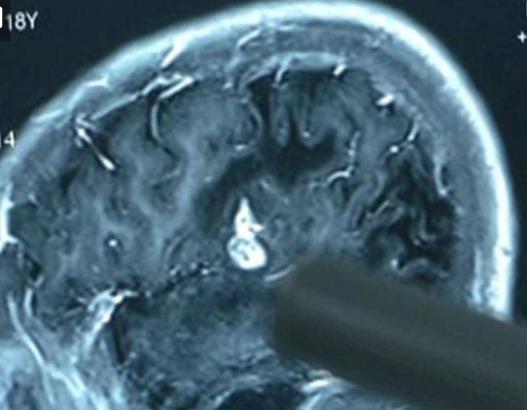

17 عاما من المعاناة والسبب "دودة شريطية في الدماغ"